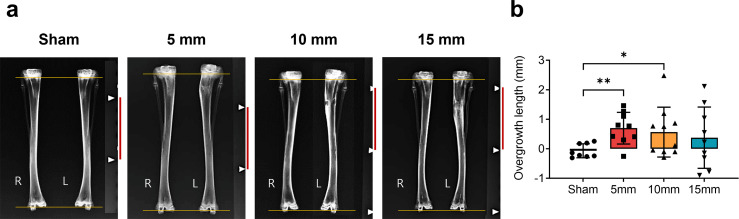

Methods: In Experiment 1, 38 skeletally immature male New Zealand white rabbits were randomized into one of four groups: a metaphyseal hole created at 5, 10, or 15 mm distal to the physis of the left proximal tibia with the hole filled with bone wax, or a sham control group. In Experiment 2, after establishing the distance associated with the most overgrowth, a defect was created at 10 mm distal to the physis in 20 additional rabbits, which were randomly assigned to have the defect filled with Tisseel, or be left unfilled. The rabbits were euthanized six weeks postoperatively.

Results: The length and rate of overgrowth were higher in the groups with holes drilled 5 and 10 mm distal to the physis compared to the sham group. A significant increase in new bone width was observed in the 10 mm distal hole group. Growth stimulation in both radiological and histological analyses was not significant in the unfilled and Tisseel groups. Valgus deformities were observed in all groups with metaphyseal holes compared to the sham group.

Conclusion: Creating a metaphyseal hole 10 mm distal to the physis of the proximal tibia can significantly stimulate longitudinal growth and induce tibia valga in rabbits; however, the effect varies depending on the type of interposition material. Notably, overgrowth was significant only in the group with holes filled with bone wax. Based on this study, the location of the metaphyseal hole during ACL reconstruction or physeal bar excision could be optimized.